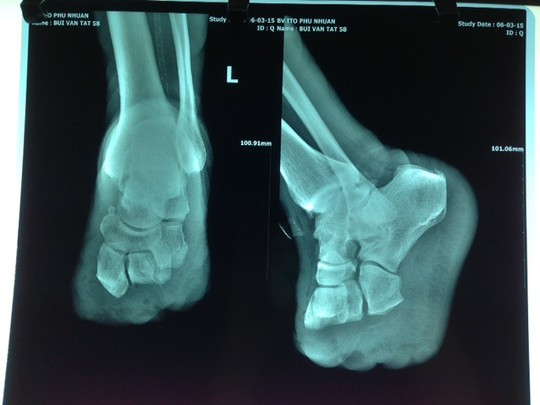

Bệnh viện Sài Gòn ITO cho biết nơi đây vừa tiếp nhận phẫu thuật loại bỏ hoại tử lan rộng thành công cho bệnh nhân Bùi Văn T. (58 tuổi, ngụ An Giang) do bị mắc bệnh tiểu đường mà không biết.

Trước đó, ngày 5-3, ông T. nhập viện với bàn chân chân trái nhiễm trùng nặng, các ngón chân số 2, 3, 4 đang bị hoại tử. Do vết nhiễm trùng quá nặng và bị hoại tử đến xương, mô dưới da, bao gân gập duỗi các ngón lan dọc đến tận giữa bàn chân nên các bác sĩ quyết định phải tháo khớp nửa bàn chân để tránh nguy cơ nhiễm trùng có thể tái phát và lan rộng cho bệnh nhân.

Chỉ vì chủ quan, bệnh nhân phải chịu cảnh tháo khớp bàn chân.